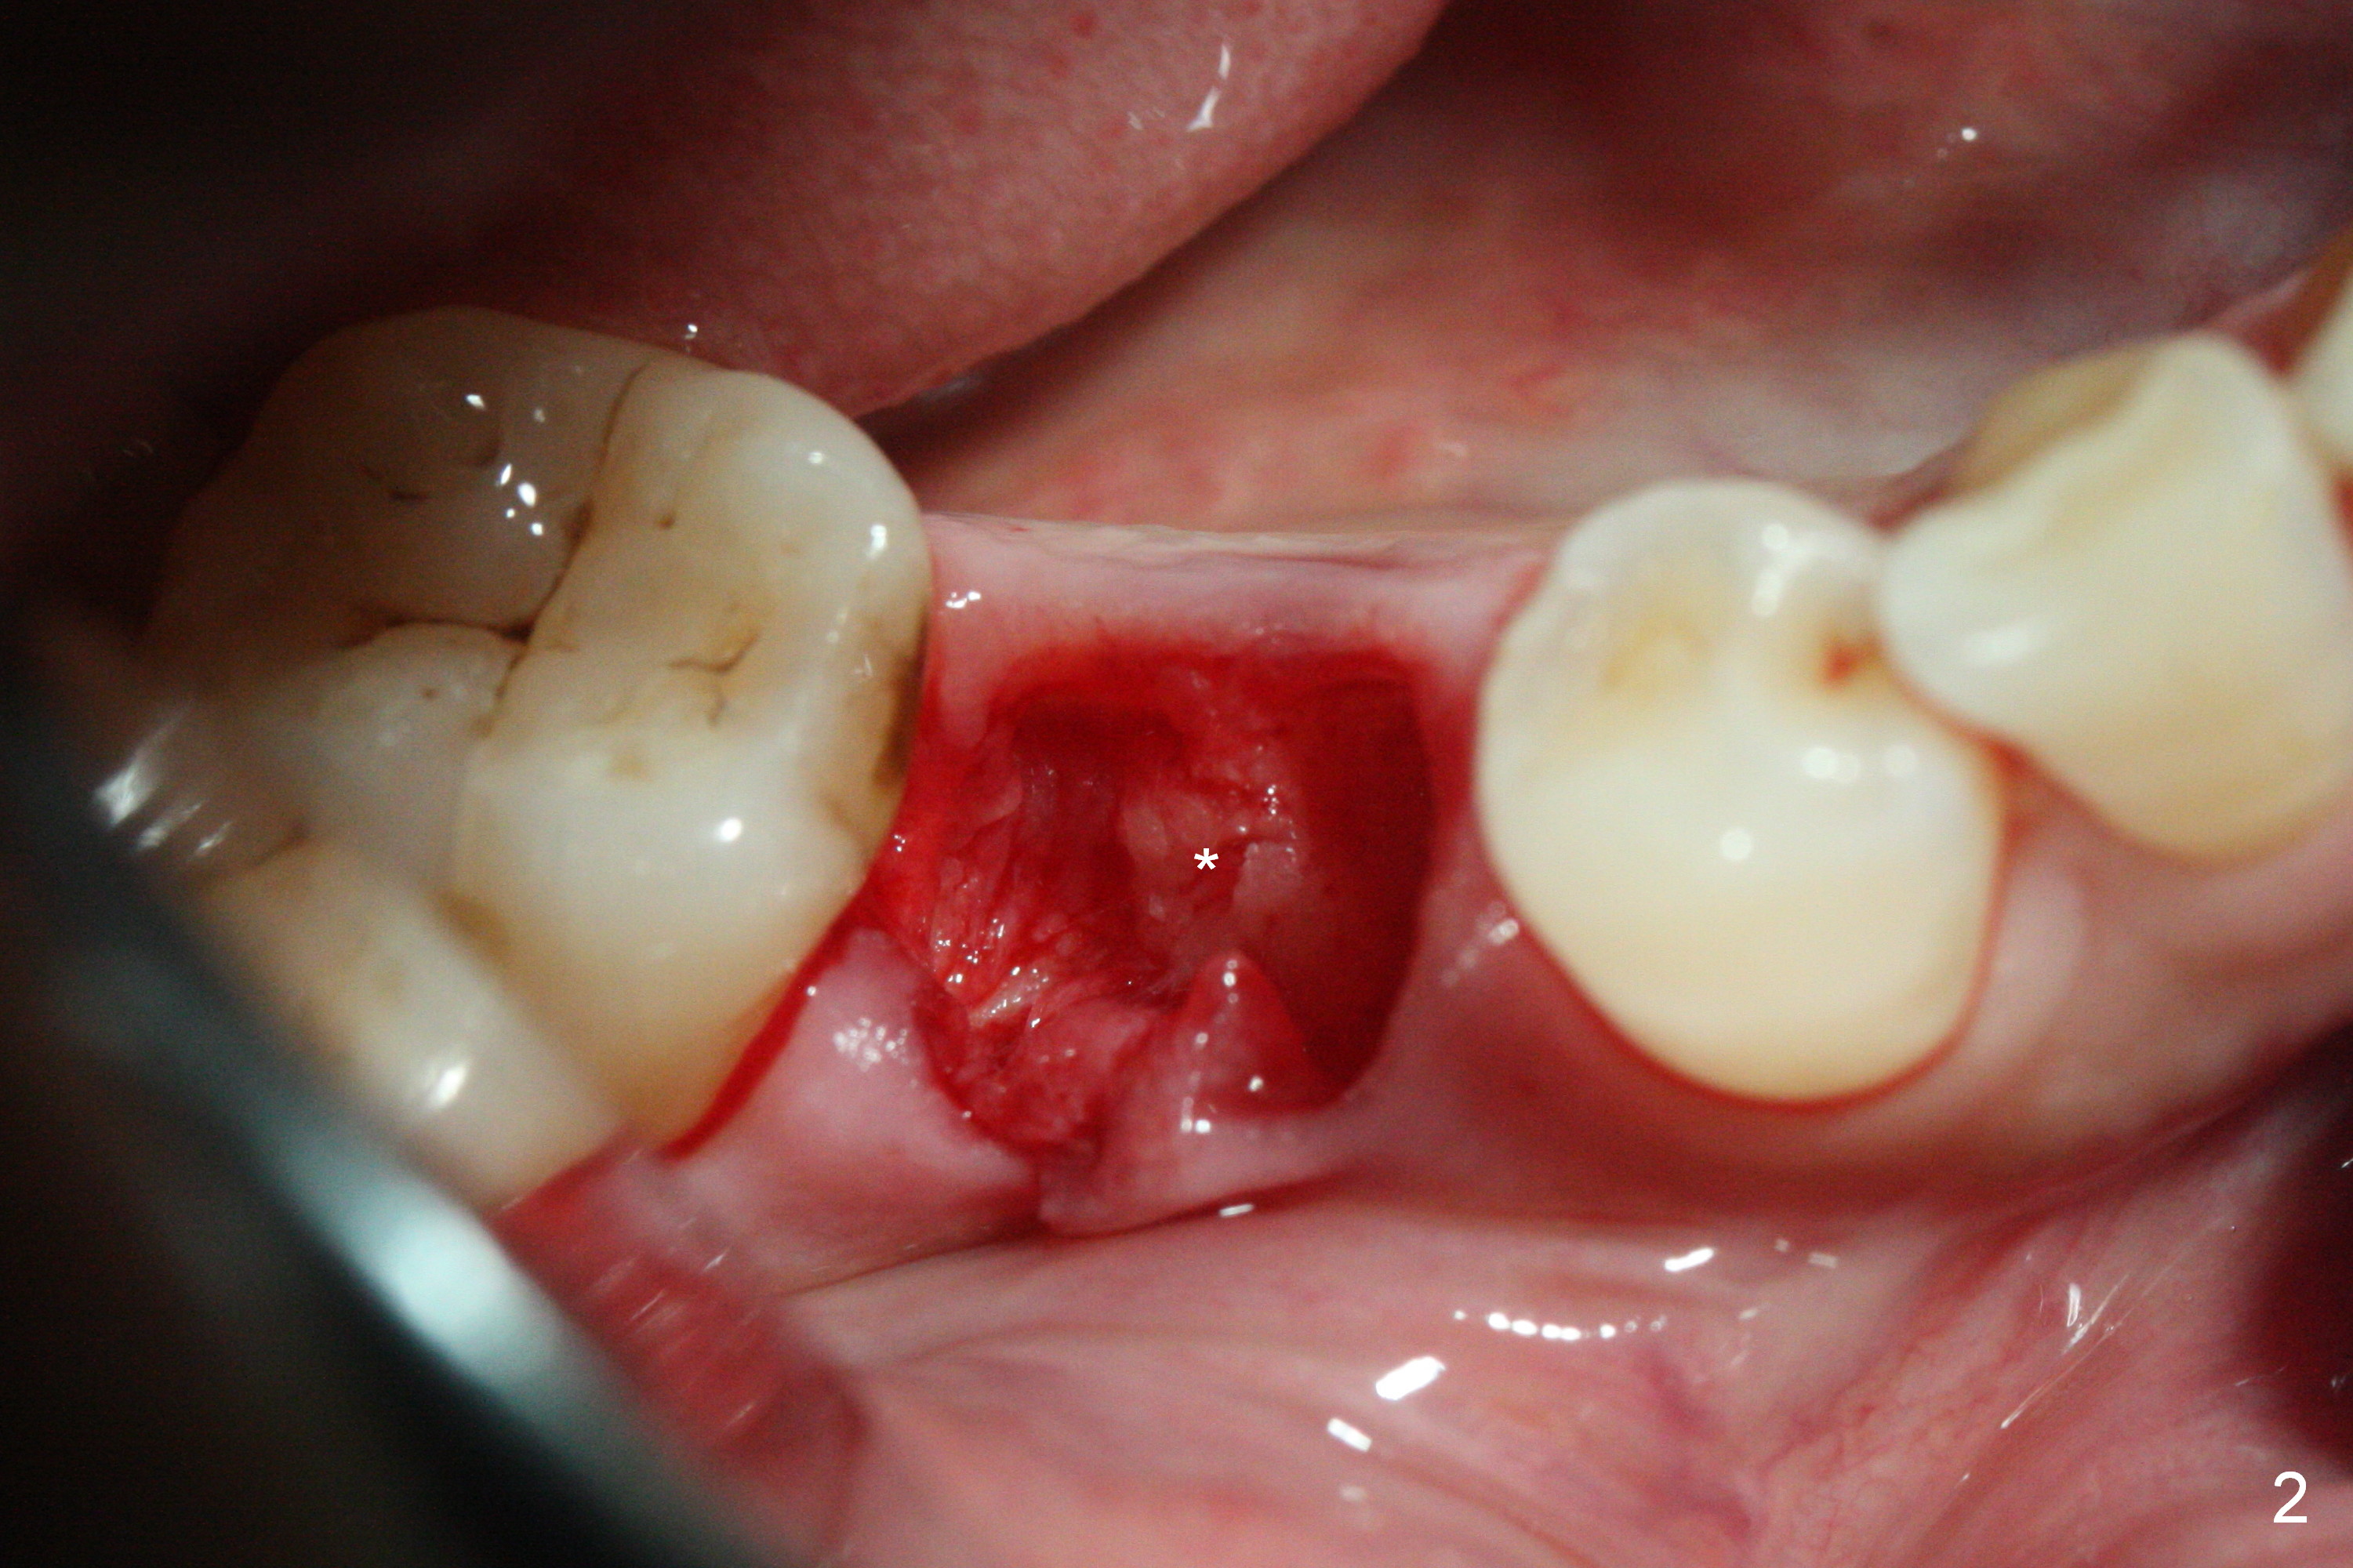

The lower 2nd primary molar has buccal furca lesion (Fig.1 *) with the thin buccal plate (Fig.2). Osteotomy is initiated in the sloped septum (Fig.3). After use of Magic Drill (MD) 3.3 mm for 13 mm and MD 3.8 mm for 11 mm, placement of a 4x11 mm IBS implant meets resistance because of the dense bone (Fig.4-6, red dashed line: Mental Loop) with final insertion torque >50 Ncm. After placement of a 6x4(3) mm abutment and autogenous bone in the remaining shallow sockets (Fig.6), a provisional is fabricated (Fig.7). Finally periodontal dressing is applied. Impression is taken 3 months postop (Fig.8). Buccal infection develops 2 weeks post cementation (Fig.9). When the crown/abutment is removed, there is no residual cement. The implant threads can be felt through the fistula. After soft tissue debridement and copious irrigation, Arestin is placed in the fistula. The latter disappears 15 days post debridement. The patient feels better and moves out of state. It appears that early periimplantitis develops because of the preexisting buccal furca lesion and failure to place the implant deep. The implant will be placed deep after loosening a little (since there is apical space (Fig.8 white line)) or removed, truncated at the apex and placed lower than the buccal crest.